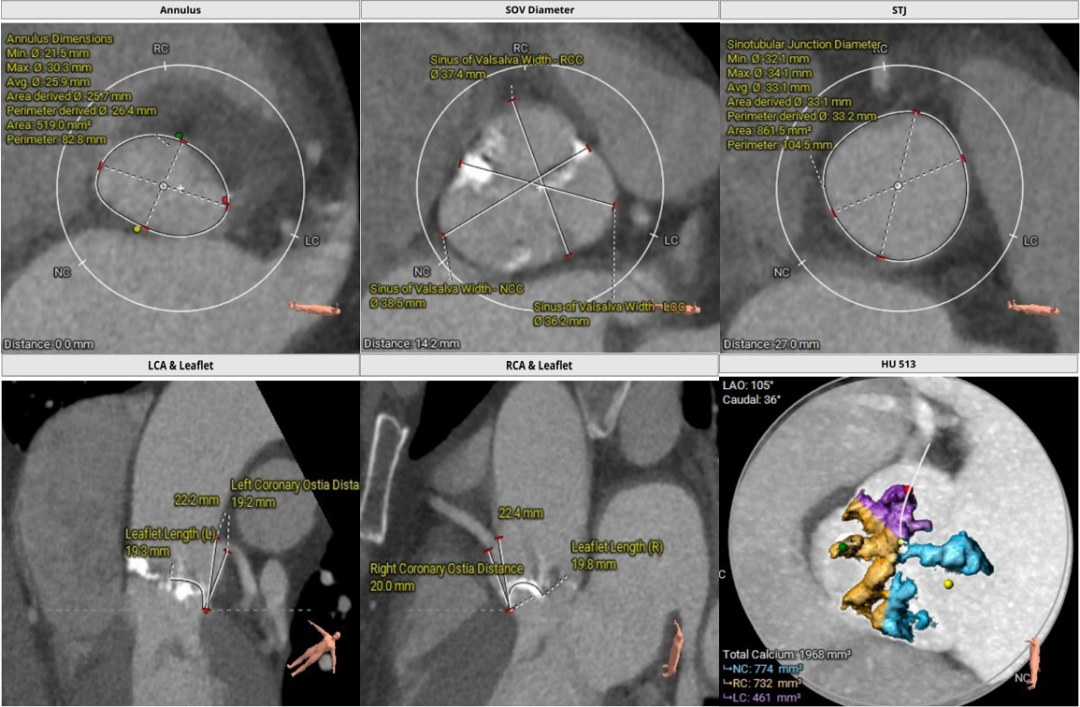

1.主动脉瓣瓣环周长82.8mm,平均周长径26.4mm。

2.主动脉瓣成三叶式,瓣叶增厚明显钙化,左右钙化融合。

3.左右冠脉开口高度可,未见瓣叶冗长。

主动脉根部评估:

瓣环上解剖结构评估: